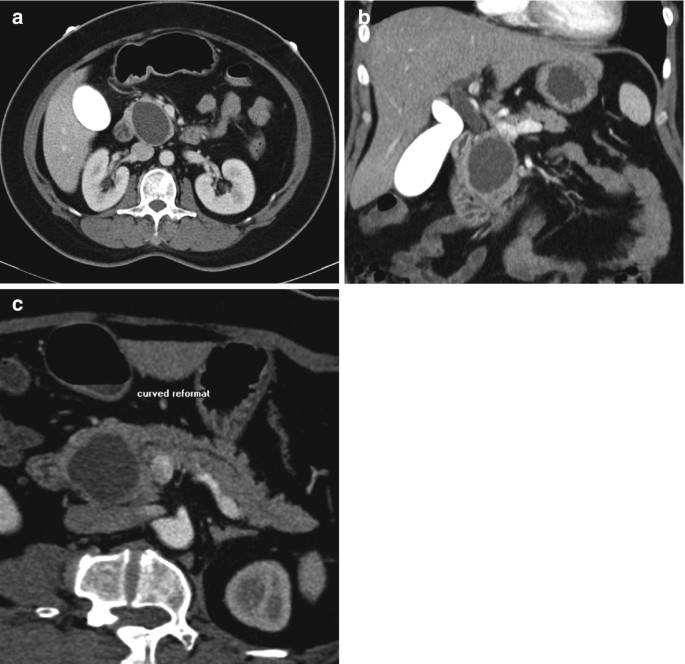

From link.springer.com

Retroperitoneal Lesion Containing Macroscopic Fat and Calcification Differentials For Abdominal Pain Several other pivotal points can help narrow the differential diagnosis including (1) the time course of the pain, (2) peritoneal findings on exam, (3) unexplained hypotension, and (4) abdominal. Learn how to approach the differential diagnosis of abdominal pain in adults based on history, physical examination, and. Learn how to make differential diagnoses based on the regional location of your. Differentials For Abdominal Pain.